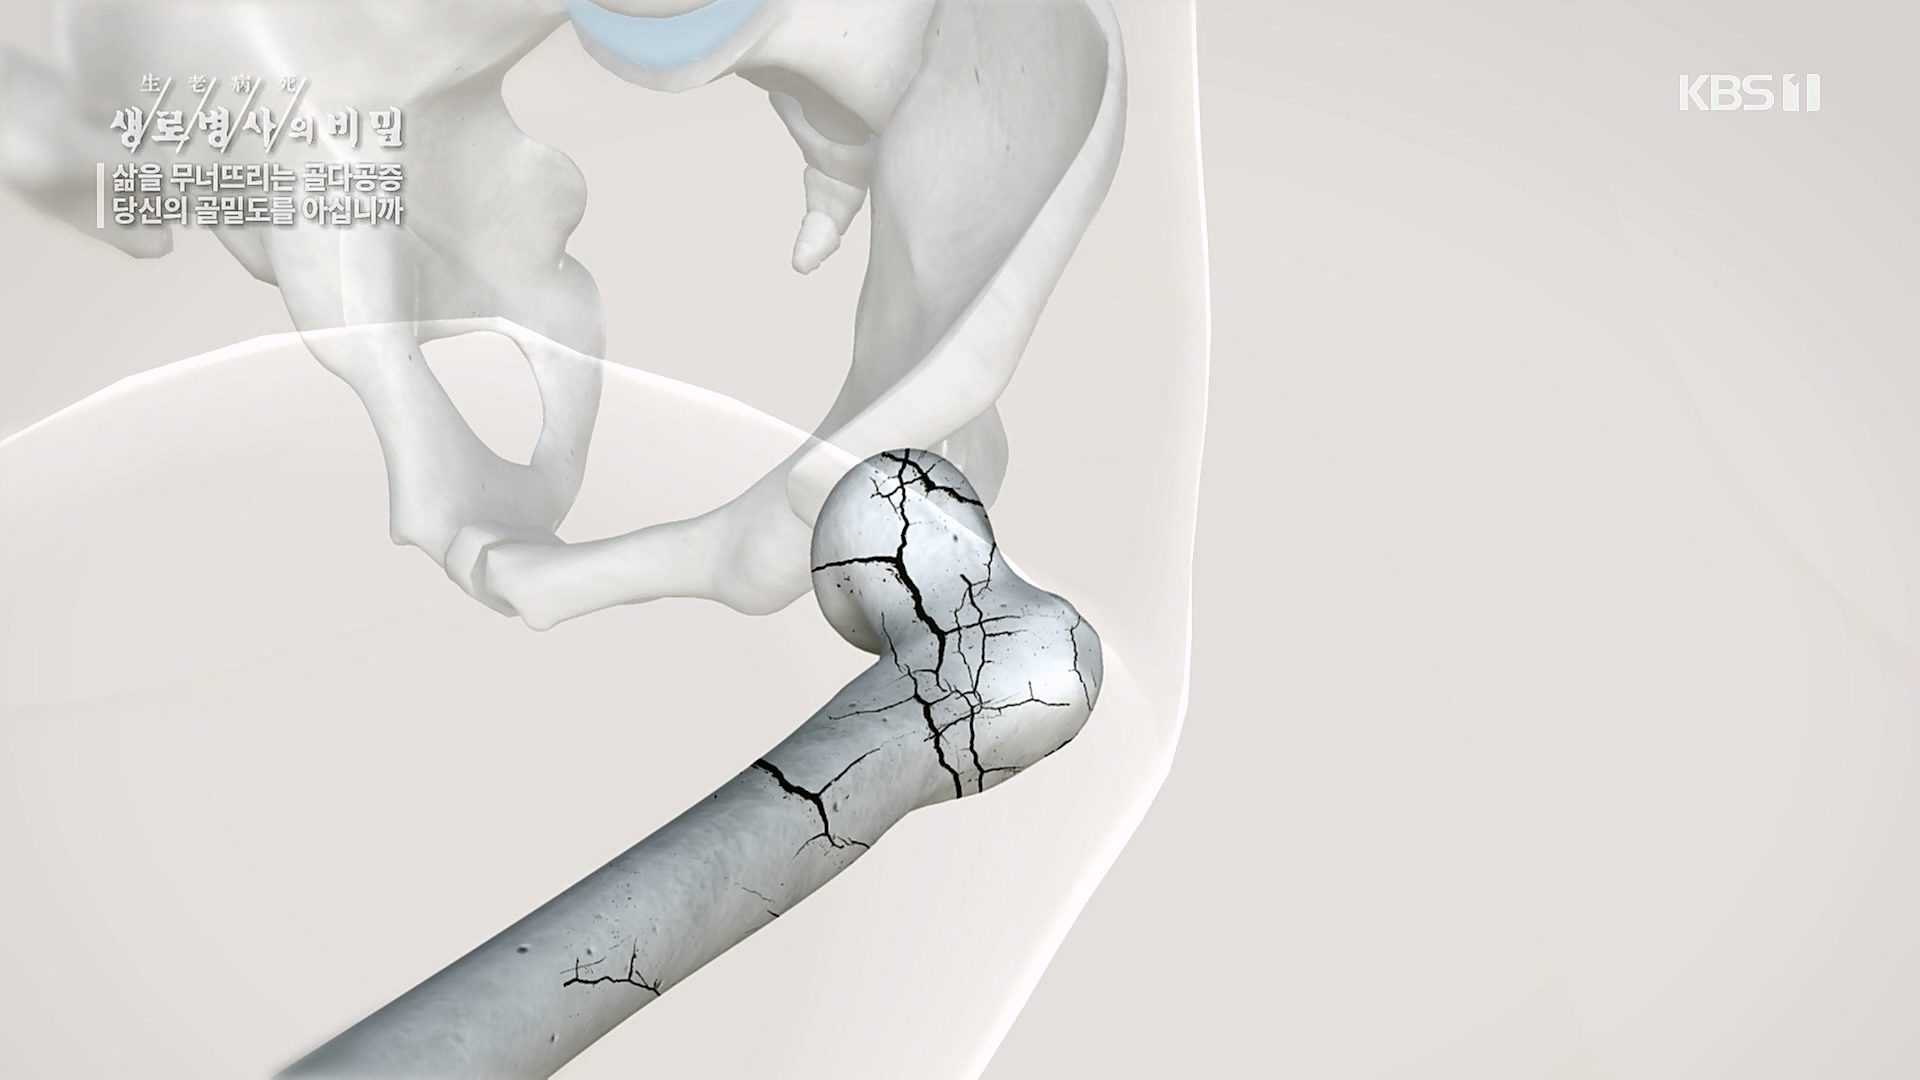

고관절골절을 당한 10명의 노인 중 1년 이내에

김용찬 | 강동경희대학교병원 정형외과 교수